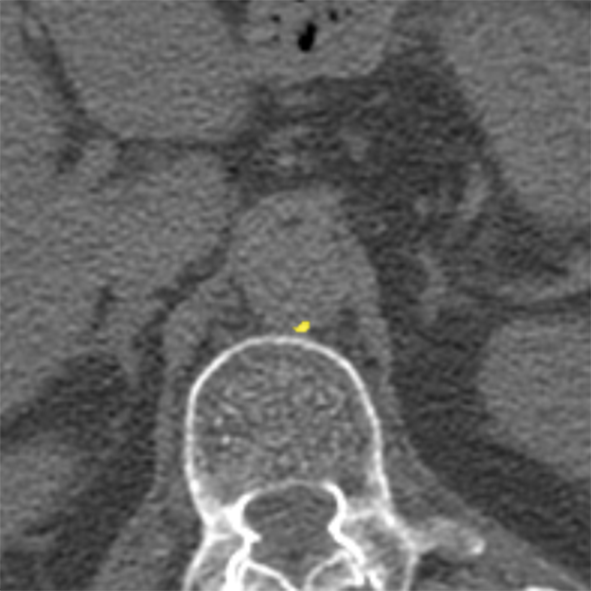

To establish a reference standard, calcifications were manually labeled in all scans. Scans were distributed among four trained observers and one radiologist with extensive experience in calcium scoring. To measure interobserver agreement, a subset of 100 scans (four scans from each of the 25 different scanner models and reconstruction algorithms) was annotated by two of the trained observers and the radiologist. Manual calcium annotation usually requires the observer to select only a single voxel per lesion. The lesion is then automatically segmented with region growing using the standard intensity threshold of . In low-dose scans, however, intensity based region growing often leads to large amounts of noise being segmented with the calcium (Figure 1). Moreover, it can lead to the spine and ribs being segmented together with calcium, or calcifications in arteries branching off the aorta being segmented together with calcium in the aorta. The observers therefore marked calcifications voxel-by-voxel () in the coronary arteries, the aorta and the aortic and mitral valves, including the annulus. Coronary calcifications were labeled as either left anterior descending artery (LAD), left circumflex artery (LCX) or right coronary artery (RCA). The left main coronary artery was considered part of LAD because these are difficult to distinguish on ungated scans. Motion artifacts caused by calcifications were annotated as calcifications because an exact separation of true calcification and artifact is often not possible. Depending on the amount of calcification and the image quality, the annotation effort varied from 5–10 minutes for images with soft reconstruction and little calcium to 60–90 minutes for images with sharp reconstruction and/or large amounts of calcium.

The performance of automatic CAC detection was evaluated based on scores per artery and per subject. Per artery and per subject sensitivities, average false positive volumes and F1 scores for CAC detection are listed in Table II. Examples of detected calcifications are shown in Figure 6.

(a)

(b)

(c)

(d)

(e)

(f)

(g)

(h)

(i)

(j)

(k)

(l)

For CAC and TAC detection, the method achieved a performance close to the level of interobserver agreement. The method was furthermore able to separate calcifications in the coronary arteries into LAD, LCX and RCA calcifications (Figure 6 (f)). The method as well as the observers were more successful in identification of LAD and RCA calcifications than LCX calcifications. The course of LCX is particularly difficult to follow in non-contrast scans. Hence, LCX calcifications can be difficult to differentiate from LM and LAD calcifications (Figure 6 (l)), as well as from those in the mitral valves. In comparison to CAC and TAC, calcifications of the aortic and mitral valves were less common in our dataset. Performance of the automatic method was below the performance of CAC and TAC detection. However, this is also a difficult task for experts. The observers especially disagreed on mitral valve calcifications, which is in line with findings of previous studies [45]. The disagreement is mainly caused by confusion with LCX calcifications and the lack of soft tissue contrast in the mitral valve region. For the aortic valve, confusion with TAC was the most common cause of disagreement.

False positive detections were mostly caused by mislabeling of calcifications with respect to their location (e.g., LAD and LCX), low-dose and motion artifacts, and other calcifications such as calcified lymph nodes or calcifications in other vessels (Figure 6 (i)–(k)). False positive detections outside the heart and the aorta occurred infrequently and usually in proximity to the heart or the aorta. This demonstrates that CNN1 was able to implicitly learn to recognize the typical spatial context of calcifications in the image. The individual evaluation of CNN1 additionally showed that CNN2 substantially contributes to reducing false-positive detections while maintaining a high sensitivity. However, future work could aim at unifying the two networks into a single network.

False negative detections were sometimes partially misclassified lesions (Figure 6 (h)–(i)). Partial misclassification can occur because the method performs voxel classification rather than the standardly used lesion classification. Even though voxel labeling occasionally causes partial misclassification of calcifications, it enables splitting of calcifications that are contained in more than one arterial bed, such as those partly located in the aorta and partly in the coronary arteries (Figure 6 (f)). Assigning a calcification that is partially contained in the aorta to the coronary artery could affect cardiovascular risk categorization. Similarly, assigning LM calcifications to the aorta would result in missing high risk lesions. To the best of our knowledge, this is the first method enabling splitting of the calcifications according to their arterial bed.